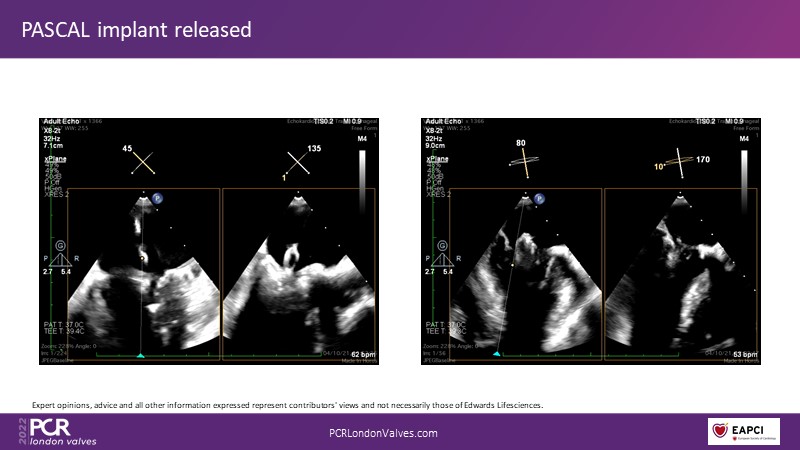

The new PASCAL Precision system unleashes the full potential of mitral transcatheter edge-to-edge repair

Join this panel of experienced physicians to learn more about the novel PASCAL Precision system and to discuss implant selection and clinical data. Finally, participate in a recorded case demonstrating the use of the PASCAL Precision system for the treatment of mitral regurgitation.